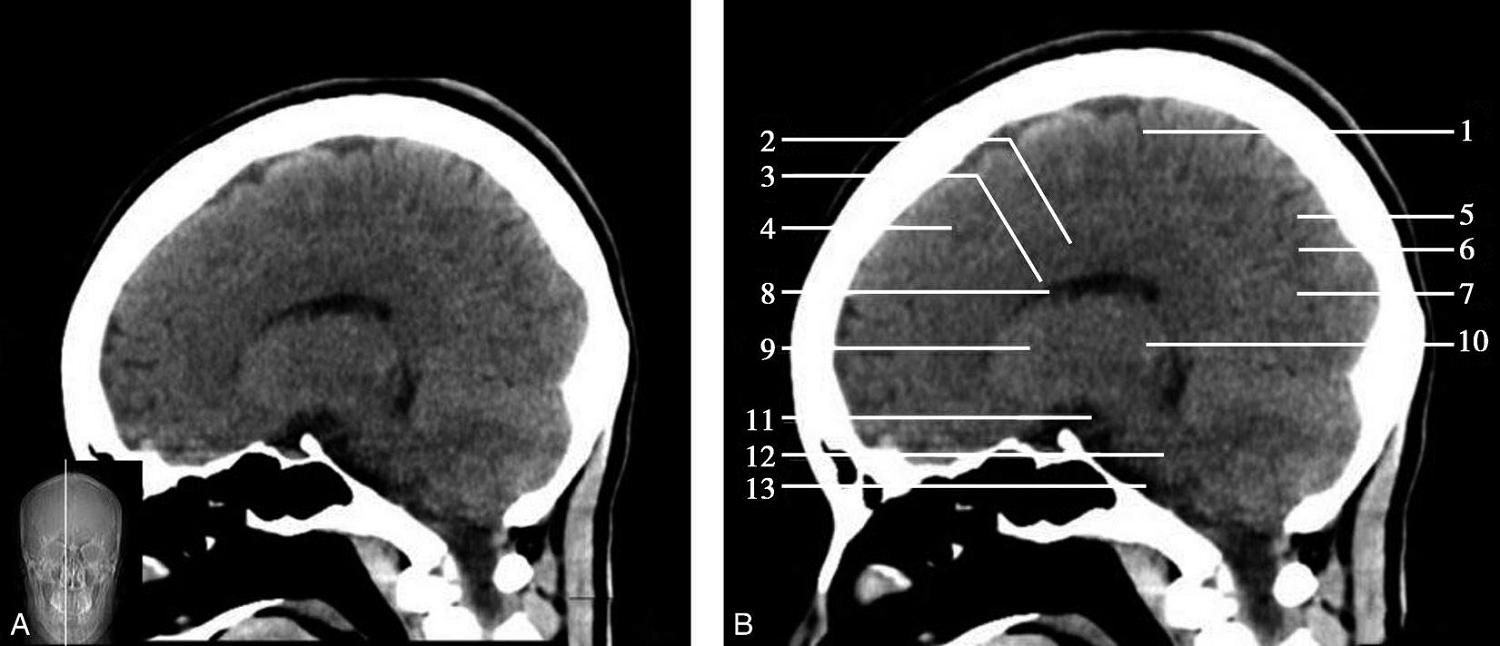

重要结构:胼胝体、垂体、中脑导水管、扣带回、中央沟、第三脑室、斜坡(图1-2-59、图1-2-60)。

图1-2-59 正中矢状面CT

A.矢状面;B.矢状面标注

1.中央沟;2.扣带回;3.胼胝体体部;4.侧脑室;5.中脑;6.胼胝体膝部;7.穹隆;8.第三脑室;9.胼胝体压部;10.垂体;11.中脑导水管;12.第四脑室;13.脑桥;14.蝶窦;15.斜坡;16.小脑扁桃体;17.延髓

图1-2-60 正中矢状面骨窗CT

1.顶骨;2.枕骨;3.斜坡;4.额骨;5.蝶鞍

此层面可显示胼胝体全貌,它位于层面中央区域,是呈上凸下凹的弧形结构,由前向后分为嘴、膝、体和压四部分。扣带回环绕胼胝体上方,扣带沟位于扣带回的上方。大脑半球中部和后部分别可见较深且恒定的中央沟和顶枕沟。中央沟为是额叶顶叶分界标志。

胼胝体下方为侧脑室及穹窿,第三脑室借穹窿与前上方的侧脑室体部分开,背侧丘脑的内侧面以及中脑顶盖分别为第三脑室的外侧壁和底。第三脑室向前籍室间孔与侧脑室相通,向下经中脑导水管通第四脑室。中脑腔狭窄呈管状,即称为中脑导水管,中脑导水管畸形,常见者为导水管的分叉畸形和狭窄,其次可见中脑导水管膈膜,造成先天性脑积水。

脑干由中脑、脑桥和延髓组成,自第三脑室底向下后稍斜行,移行于颈髓。由上至下,脑干腹侧可见脚间池、桥前池和延髓池,脑干背侧可见大脑大静脉池、四叠体池和小脑延髓池。

垂体位于蝶鞍内,其前部为腺垂体,后上部分为神经垂体。垂体下方为鞍底及蝶窦,上缘因鞍膈存在而平直,垂体借垂体柄向上连于丘脑下部。垂体的前上方见视交叉和视束。斜坡作为前颅窝底的重要组成部分与多个重要结构相比邻,矢状位呈三角形,颅内肿瘤或颅外鼻咽部恶性肿瘤均可侵犯至此,原发肿瘤常见为脊索瘤。小脑幕居枕叶和小脑之间,向后下连接窦汇,向前至中脑后方游离,称小脑幕切迹。小脑幕下方为小脑扁桃体。成年人小脑扁桃体下缘由枕骨大孔向下疝入椎管超过5mm称为Chiari畸形,以矢状位显示最佳。